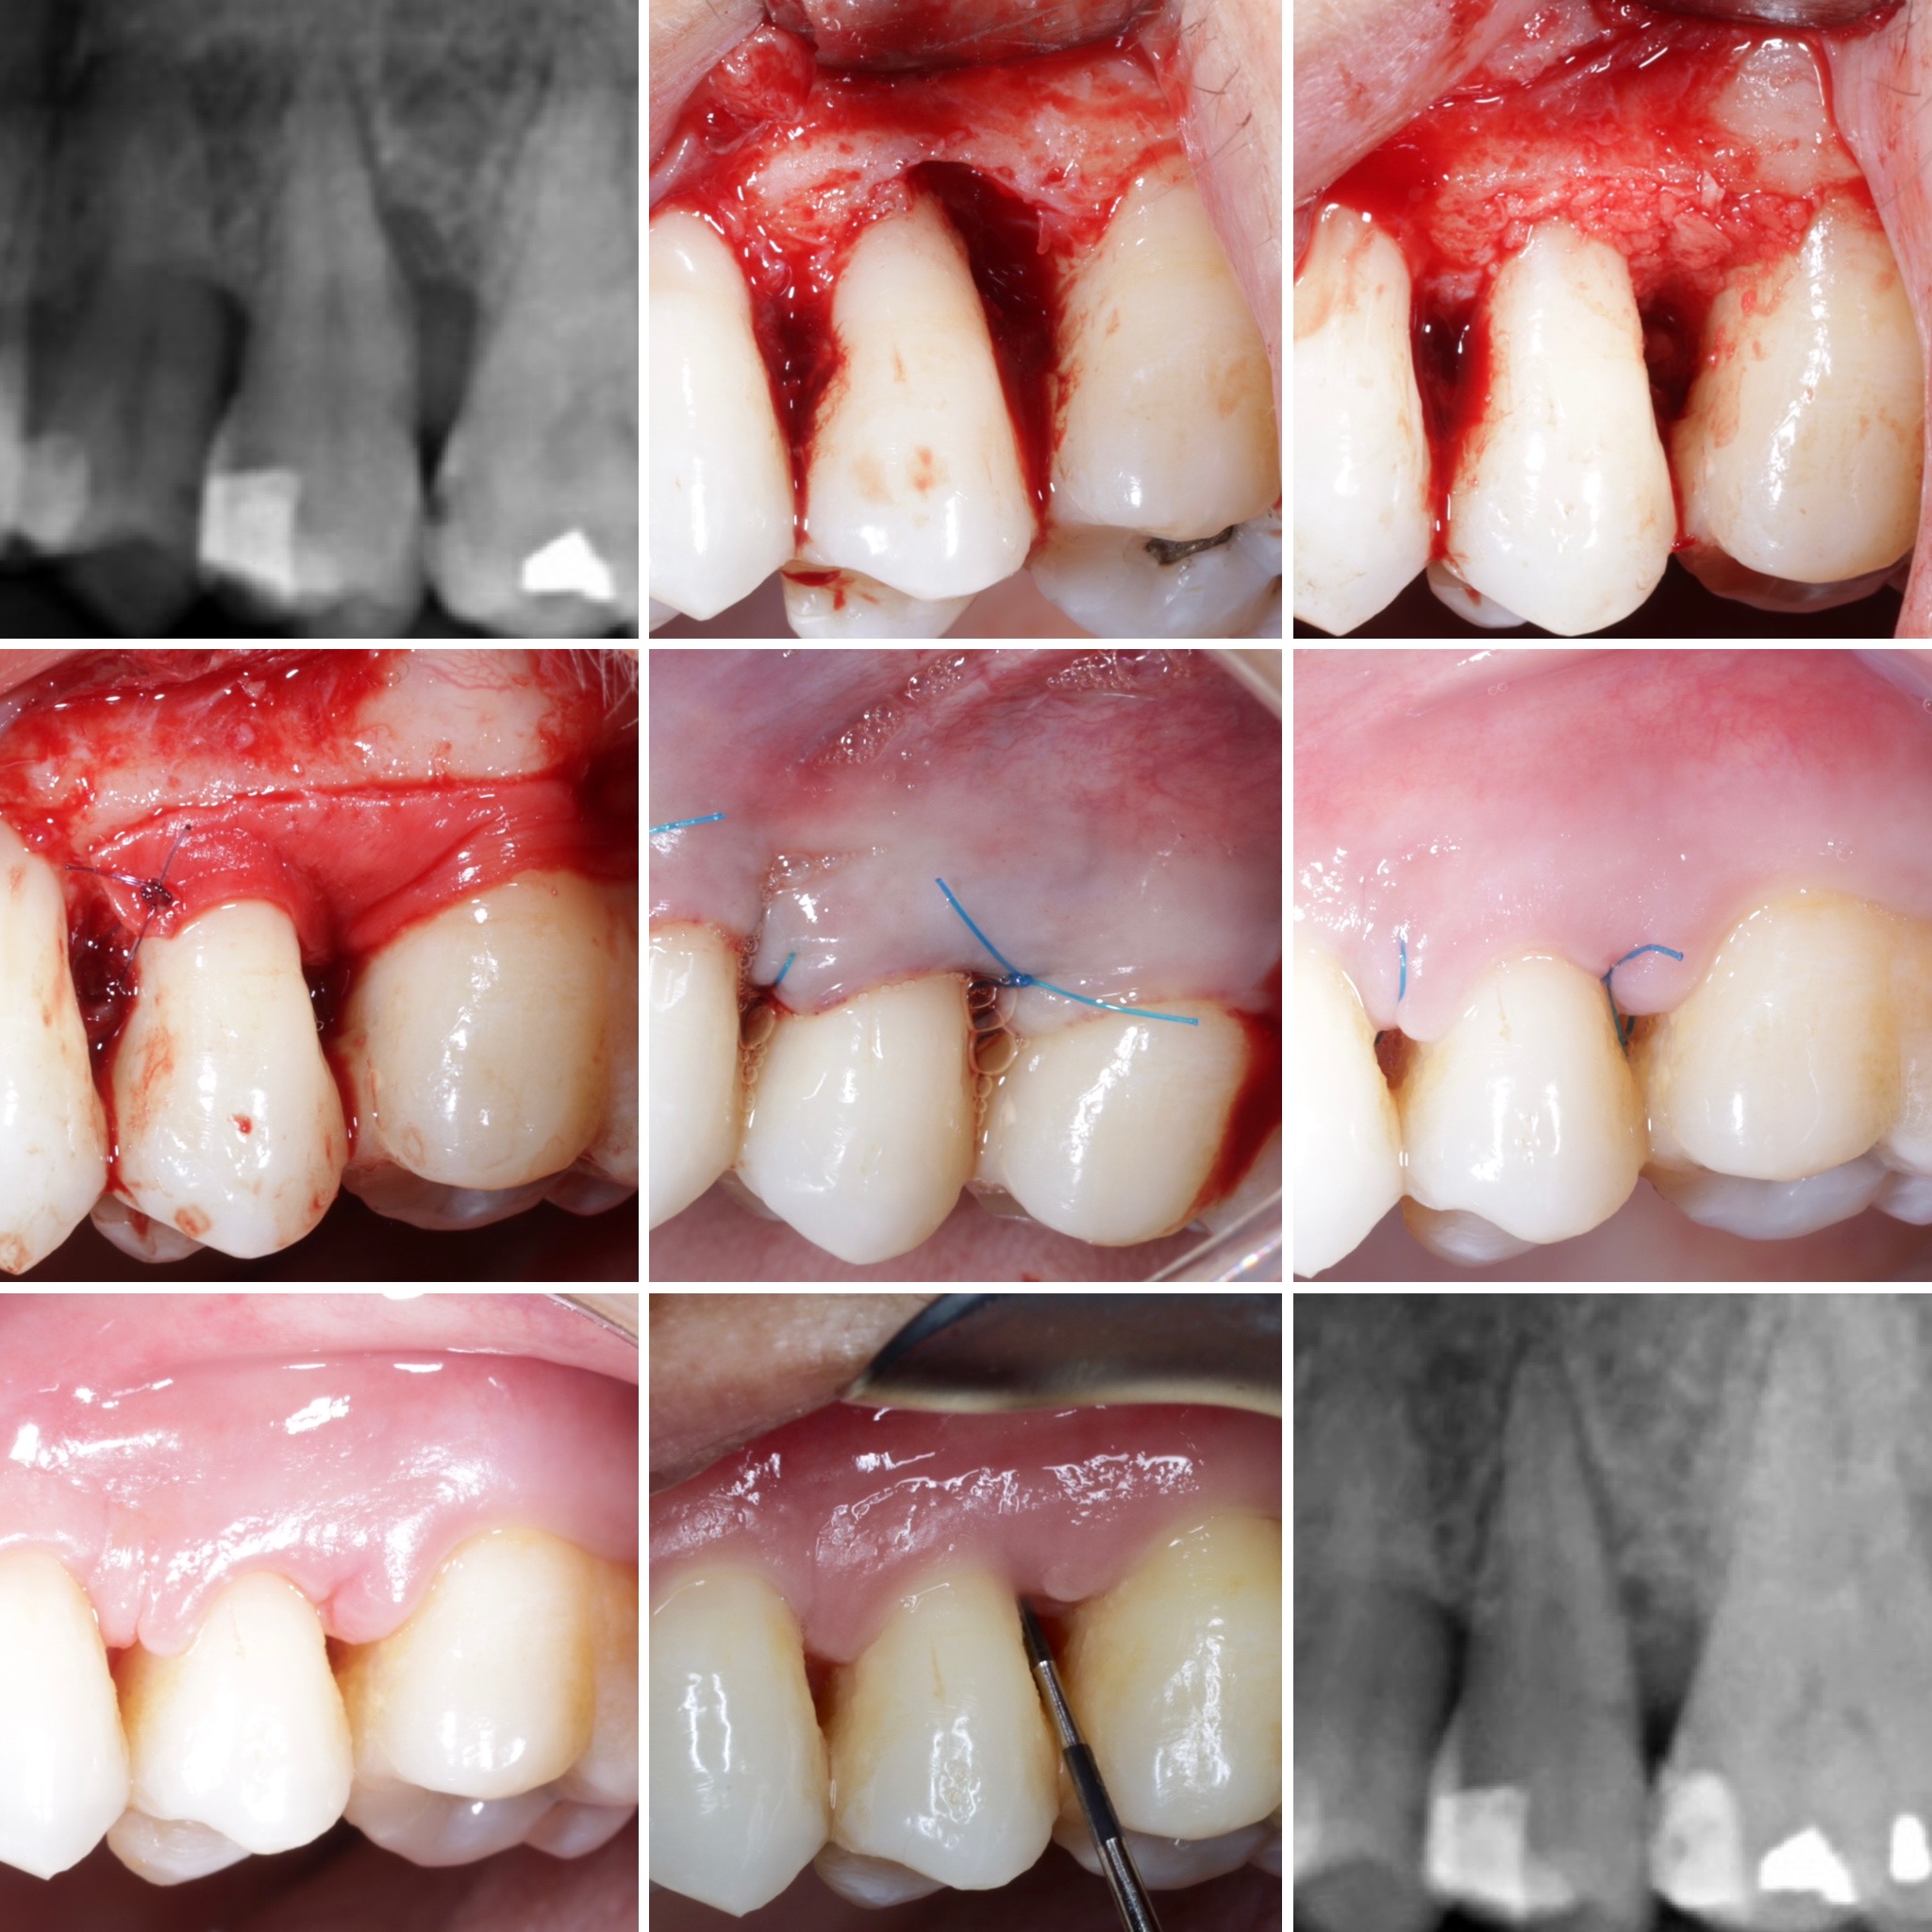

Podrás asistir a la planificación de casos y cirugía de injerto de tejido conectivo. Factores determinantes y elección de la técnica adecuada. Sumérgete en un protocolo predecible y técnicamente correcto para obtener resultados óptimos.

Ofrecemos una inmersión pura en una de nuestras pasiones, la Regeneración Periodontal, tanto para niveles iniciales como avanzados. En este modelo de estancia clínica ofrecemos una parte teórica, presentación de casos clínicos, un taller hands-on y a convenir, la asistencia a una cirugía

La formación comenzará con la presentación del caso clínico que se abordará durante el curso, seguida de una cirugía en directo, que permitirá observar paso a paso el procedimiento y la toma de decisiones clínicas. Durante la jornada se profundizará en los conceptos biológicos aplicados a

Formación teórico-práctica completa sobre las técnicas más avanzadas en cirugía mucogingival. Durante dos días intensivos, los participantes aprenderán desde la evidencia científica y la anatomía de las zonas donantes hasta la ejecución de injertos, cubrimiento radicular y aumento de